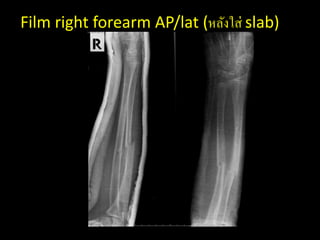

Film right forearm AP/lat (หลังใส่ slab)

Management – Pethidine 40mg IV stat – Close reduction and apply long arm AP slab right arm – Admit – Observe compartment syndrome

Film right forearmAP/lat (หลังใส่ slab)